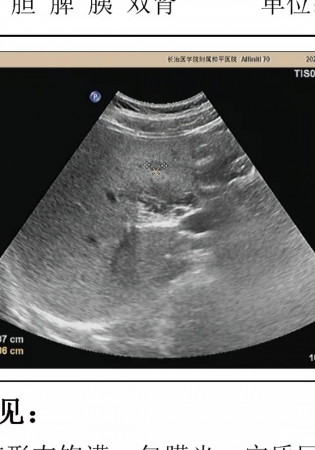

右肝低回声结节,发现后五个月彩超复查无变化,考虑什么?

肝脏低回声结节,界清,无血流信号显示,无肝病史,乙肝有抗体,甲胎蛋白正常,发现时1.0*0.7cm,两月后复查彩超0.9*0.6cm,又过了三个月复查彩超1.0*0.8cm,前后五个月无变化,有不均质脂肪肝背景,五个月减肥后脂肪肝很轻了基本没有,这低回声区像什么?可以排除肝CA吗?

四月份做了5mm增强CT,什么东西也有发现,重新让医生看了彩超,低回声很轻了找了半天才找见,而且这低回声并是不在肝右叶,而是在肝左内叶S4段,医生说可能是肝岛

三个月每天快走半个小时,复查彩超脂肪肝没了低回声区也消失了,证实是肝岛